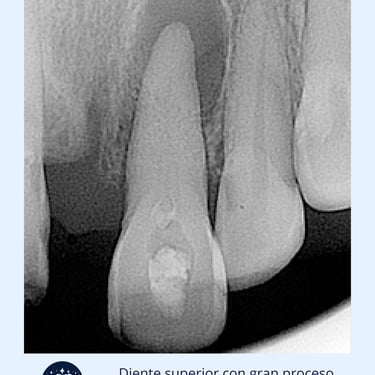

Diagnóstico clínico: El dentista examina la zona afectada y toma una radiografía para observar la lesión.

Importancia: Las lesiones periapicales, como abscesos y granulomas, se forman en el extremo de la raíz del diente. Tratarlas a tiempo es crucial para prevenir la propagación de la infección y la pérdida del diente.

Las lesiones periapicales son infecciones crónicas que se desarrollan alrededor de la raíz del diente, generalmente debido a una infección no tratada en la pulpa dental. Se manifiestan como dolor, hinchazón o un absceso.